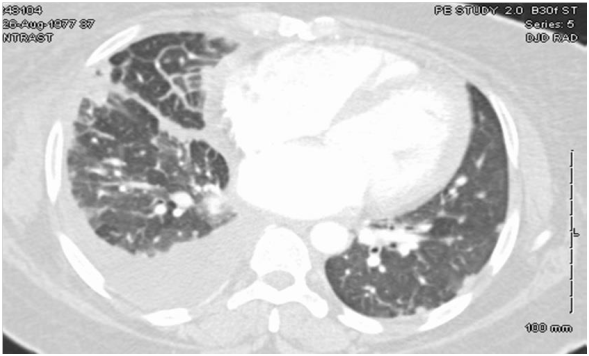

TTE showed EF of 25% with type III advanced diastolic dysfunction, further cardiac workup was done. This included cardiac catheterization which showed normal coronaries and an electrophysiological study for inducible arrhythmias which was negative. She was offered a lung biopsy; the pathology revealed classic non-caseating granulomas as shown in Figure 2.

Figure 2 Lung biopsy showing non-caseating granuloma typical of sarcoidosis. Hematoxylin and Eosin stain.